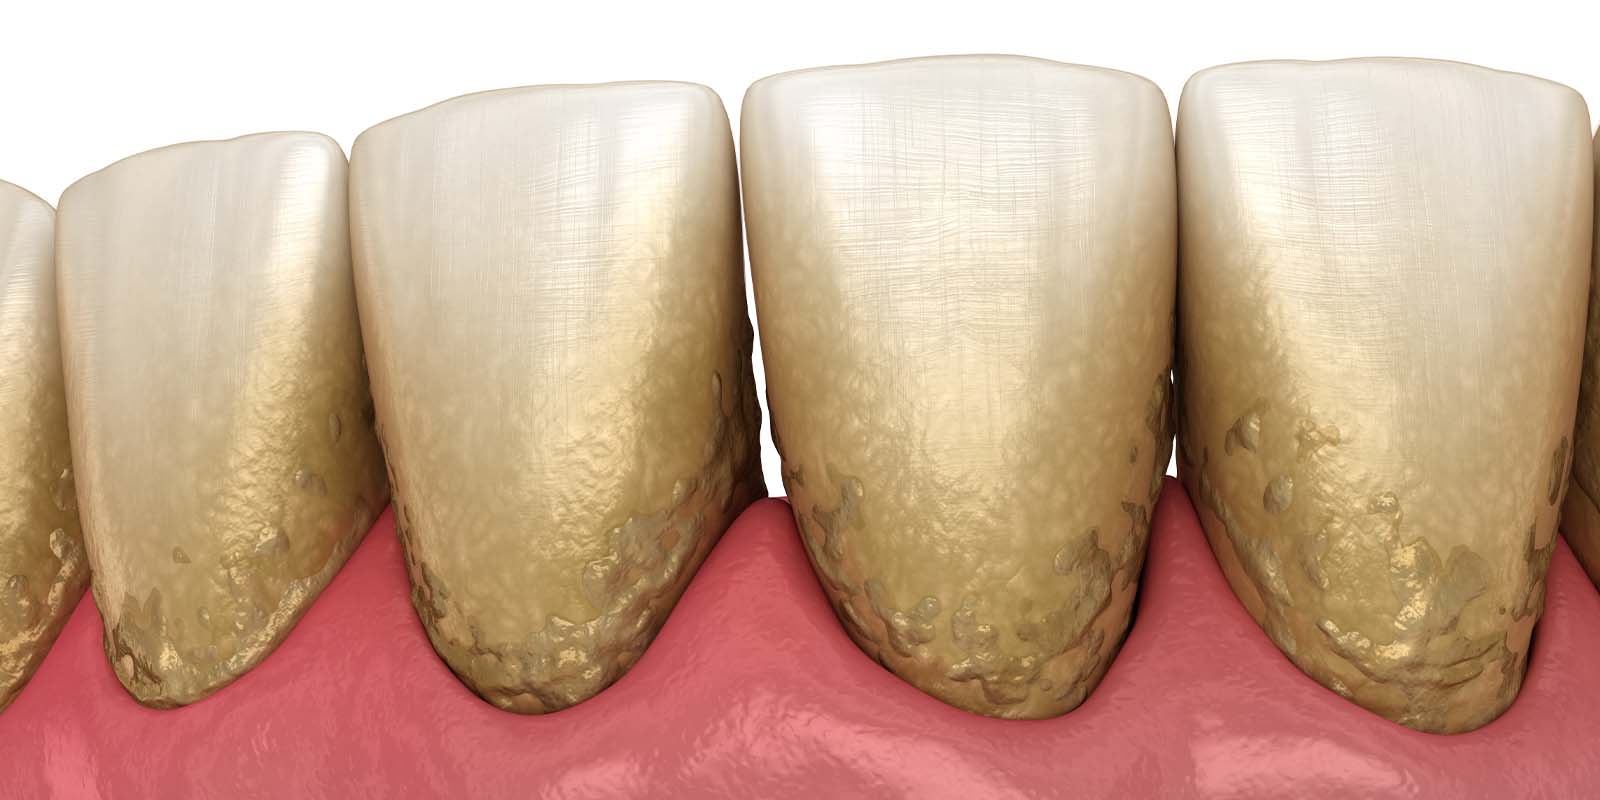

歯周病になる1番の原因は「磨き残し」です。

磨き残しのことを歯科用語では、歯垢(しこう)またはプラークといいます。

プラーク1mgのなかには、およそ300種類1億個の細菌が存在しており、歯ぐきに付着することで炎症を引き起こします。これが歯肉炎の始まりです。 つまり、お口の中に細菌が多い状態が続くと歯肉炎、歯周病の原因になります。

歯石は歯垢(プラーク)が石灰化したものです。

大量の細菌が含まれていますが、歯ブラシの力では除去することができません。

特に歯周病の場合は、歯ぐきの中に歯石が入り込むため、気づかずに放置してしまう方も少なくないのです。

歯周病を悪化させないためにも、定期的なクリーニングで歯石の除去をおすすめします。